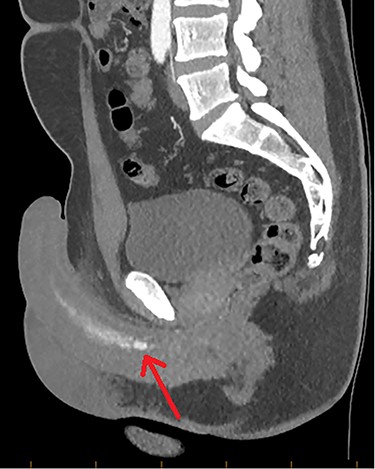

A 28-year-old gentleman presented with a non-tender, persistently rigid penis 2 weeks after a blunt force injury to his perineum. There was no penetrative damage or other symptoms, with an unremarkable background medical history. Pain-free and well, initial investigation with Doppler ultrasound (US) was sought. US demonstrated some hypoechoic tissue within the corpus cavernosum, but otherwise there was no other soft-tissue abnormality. Colour Doppler did however find an abnormally low peak-systolic-velocity (PSV) in the left cavernosal artery. As such computed tomography angiography (CTA) was arranged, showing an asymmetrical arterial-phase blush within the proximal portion of the left corpus cavernosum, neighbouring the left cavernosal artery (Figs 1 and 2). With no other radiographic genitourinary abnormality, HFP was diagnosed, secondary to arterial pseudoaneurysm.

CTA demonstrating a sagittal view of contrast enhancement within the region of the left cavernosal artery and mid-to-distal corpus cavernosum (red arrow).